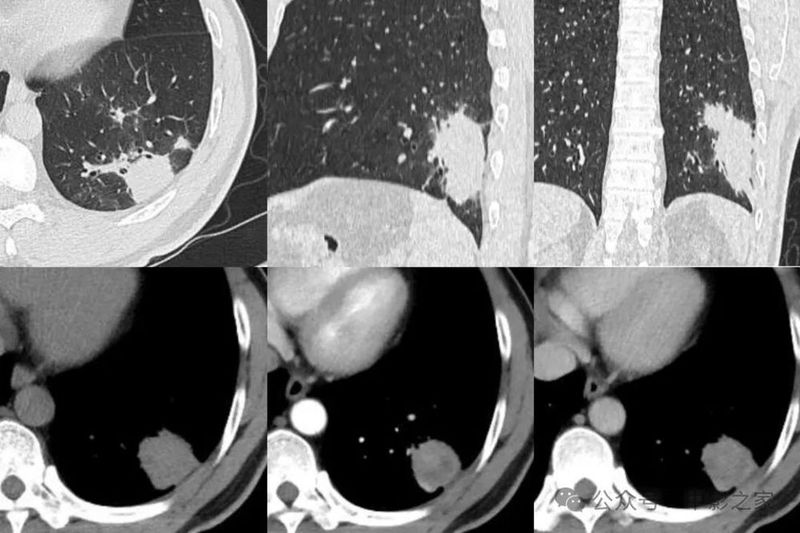

三、弥漫粟粒型

粟粒性结节呈弥漫分布,此类型较为少见。

四、混合型

混合病变,分布于肺外带,表现为结节、肿块、半片、大叶实变多样化病灶共存。